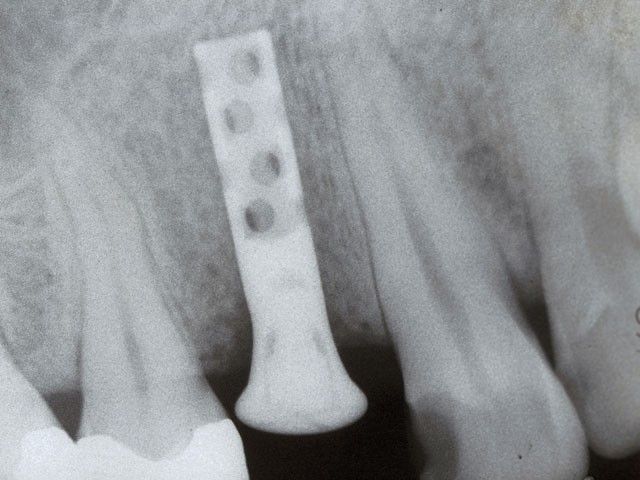

«Το πρώτο μας εμφύτευμα στην Κρήτη»

“Στις παρακάτω φωτογραφίες προβάλλονται δύο παλιά περιστατικά. Το πρώτο είναι το πρώτο μας εμφύτευμα και είναι το μακροβιότερο από όσα έχουν τοποθετηθεί στην Κρήτη! Το δεύτερο είναι μια μεγαλύτερη αποκατάσταση από το 1997”

ΠΡΩΤΟ ΠΕΡΙΣΤΑΤΙΚΟ